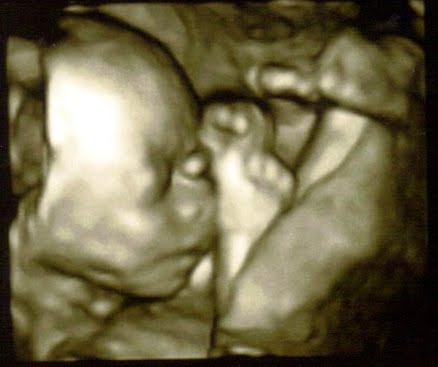

Here is my little man below: